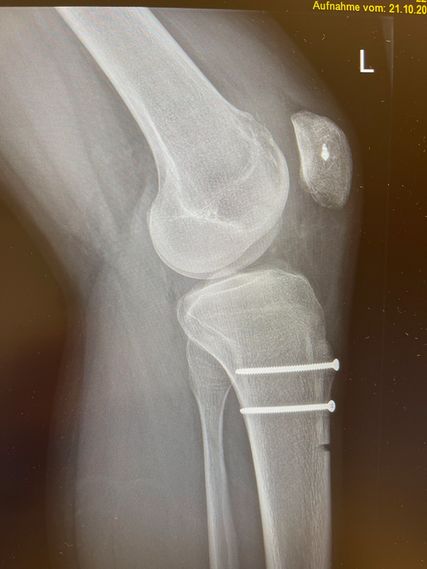

Bei der Patella alta wird der Ansatz knöchern etwas nach distal versetzt. Die Schnittführung ist lateral parallel zur Tuberositas, die Osteotomie erfolgt tangential unter Schonung der Patellasehne. Als Führung können 2 Kirschnerdrähte parallel entlang der Schnittführung eingebracht werden. Vor der Operation wird als Anhaltspunkt die gewünschte Distalisierung errechnet. Es empfiehlt sich jedoch, intraoperativ den Patellastand mittels Bildwandler zu kontrollieren (Ziel ist ein Caton-Deschamp-Index unter 1). Die endgültige Fixierung erfolgt mit zwei 3,5-mm-Schrauben (Abb. 9).8